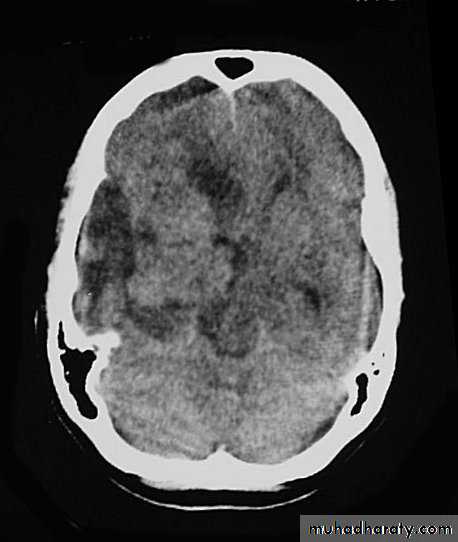

Metastatic Brain Tumours Pre contrast CT

Metastatic Brain Tumours Post contrast CT